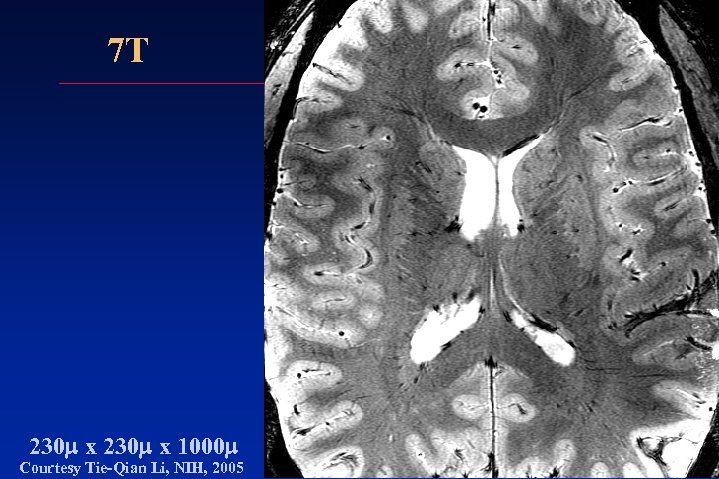

7 T 230 m x 1000 m Courtesy Tie-Qian Li, NIH, 2005 7 T 230 m x 1000 m Courtesy Tie-Qian Li, NIH, 2005